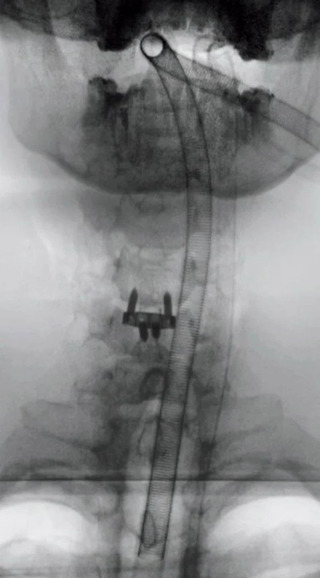

Операція пройшла успішно — блогеру встановили імплант у шию. Після втручання він вийшов на зв’язок із підписниками та показав кадри з операційної і періоду відновлення. Зараз на шиї у нього видно медичний пластир, однак сам він повідомляє про покращення самопочуття.